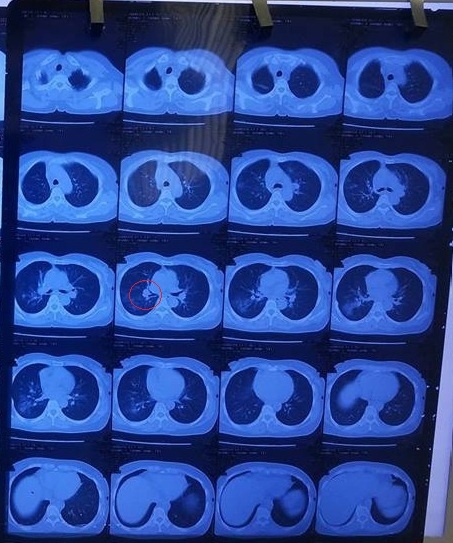

BN được uống Kilcel 500mg và khám lại tháng 3/2018 tại BVBM.

Kết quả: Không còn tổn thương di căn phổi, không còn tổn thương hạch trung thất sau 03 tháng uống Kilcel 500mg.

Kết quả chụp CT sau khi uống Kilcel 500mg 3 tháng